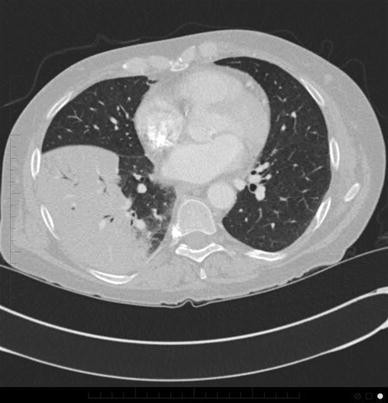

Pod pojmem legionella je myšleno přibližně 60 typů různých bakterií, přičemž minimálně 20 z nejčastějším původcem infekcí je legionella pneumophila. Relatively nonproductive cough dyspnea pleuritic or non pleuritic chest pain confluent or patchy. Legionella została zbadana po raz pierwszy w 1976 roku. This page covers what legionella is, where it grows, and how it spreads, along with its long term impact on health. Ta je zkoumána od roku 1976, kdy se jí v. Regular maintenance and testing of water systems. It's caused by the bacterium legionella pneumophila found in both potable and nonpotable water more hospitals are facing the dilemma of legionella outbreaks as they discover the drinking water is. Un morto per una polmonite legata al batterio, 16 i casi.